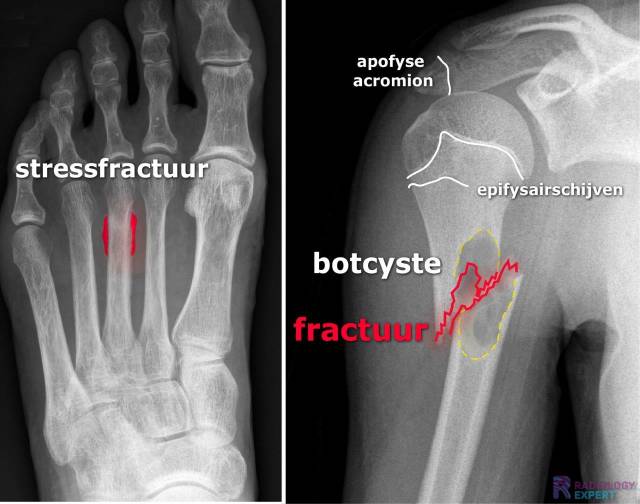

• Stress fractuur

• Pathologisch fractuur

Figuur 1. Laterale en anterior-posterior opname van de linker onderarm/pols. Een kind (9 jaar oud) met distale radiusschacht & ulnaschacht fractuur. Beide tonen een dorso-ulnaire dislocatie over circa een schachtbreedte.